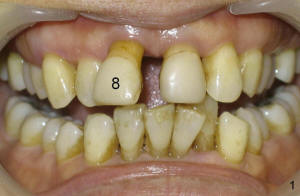

This article reports design of a simple semilunar incision for implant uncover to help form a natural-looking gingiva around anterior crown. A fifty-year-old lady has severe periodontal disease, complicated with endodontic lesion of the teeth #8 and 9 (Fig.1,2). #8 is extracted and Bicon 4.5x8 mm implant (Fig.3: I, Boston, Massachutte) is placed with bone expansion (Tatum Surgical, Clearwater, Fl) 1 year later . After RCT retreatment for #9 (compare Fig.2,3: black arrowheads), periapical radiolucency (Fig.2: red arrowhead) resolves (Fig.3).